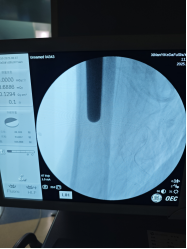

8月8日,一场精密的"生命保卫战"打响。由骨科尹一然教授领衔,联合麻醉科、心血管内科、肾内科等专家制定方案:既要取出刺入盆腔的钢钉,又要解决髋臼缺损和骨量流失难题,还要确保新关节稳固。

将患者自身修剪后的股骨头骨质填补到髋臼破损处,重建"地基";

植入特制加长股骨柄假体,像"钢筋"一样牢牢固定新关节。

3小时后,手术圆满成功! 术中出血量控制理想,老人生命体征平稳。更让人惊喜的是,术后第二天邱婆婆就能自主屈伸双腿,疼痛明显缓解。"没想到还能再站起来!"家属紧握医生的手连连道谢。